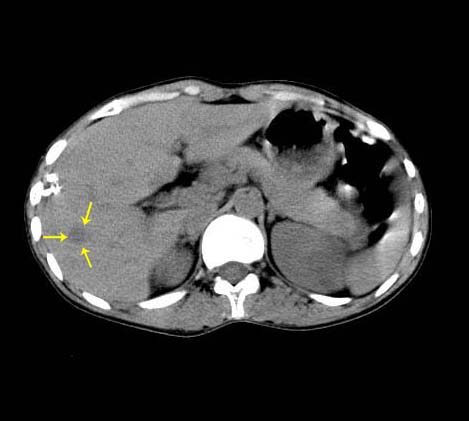

病人资料:女 30岁 右上腹部疼6天余.无其他不适,我院血常规正常,胸片正常,b超示1,肝内多发性结石.2,肝实质内似见结节影,占位病变待定.

考虑:1、肝右叶前段包膜下钙化灶;

肝右叶小圆形低密度影,建议增强扫描

肝右叶前段包膜下钙化灶;做ct增强或mri。